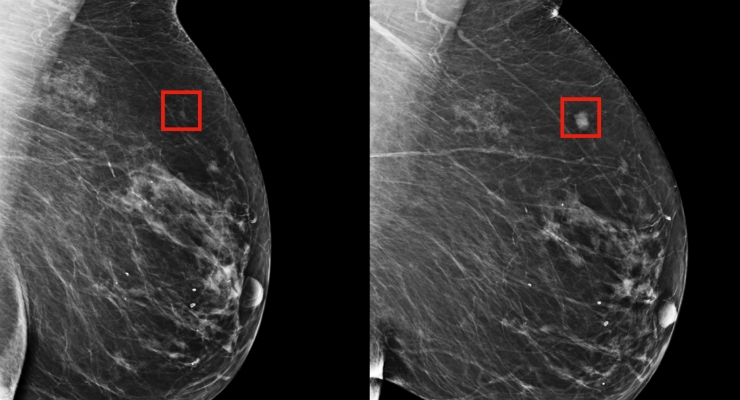

أصيبت مؤخرا بسرطان ثدي مرحلة ثانية وتحتاج لتغطية مصاريف العلاج بشكل عاجل قبل ازدياد انتشار الورم وتفاقمه.

تعاني الحالة من وجود سرطان ثدي مرحلة ثانية وتحتاج حاليا لعمل خزعة وصور اشعة رنين ومسح ذري وعلاج مستمر. وتحتاج المريضة لعلاج هرموني لمدة 5 سنوات وتدخل جراحي بعد شهرين من بدء العلاج الهرموني ومتابعة مستمرة.